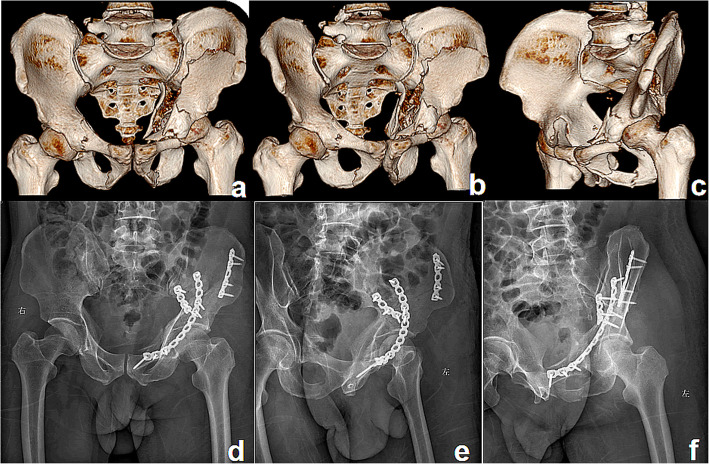

Fig. 4.

A patient treated with the S+IF approach. Preoperative 3D computed tomography reconstructions (a–c) of a both-column fracture showing the severity of fracture displacement. Postoperative radiographs (d–f) showing good reduction and fixation